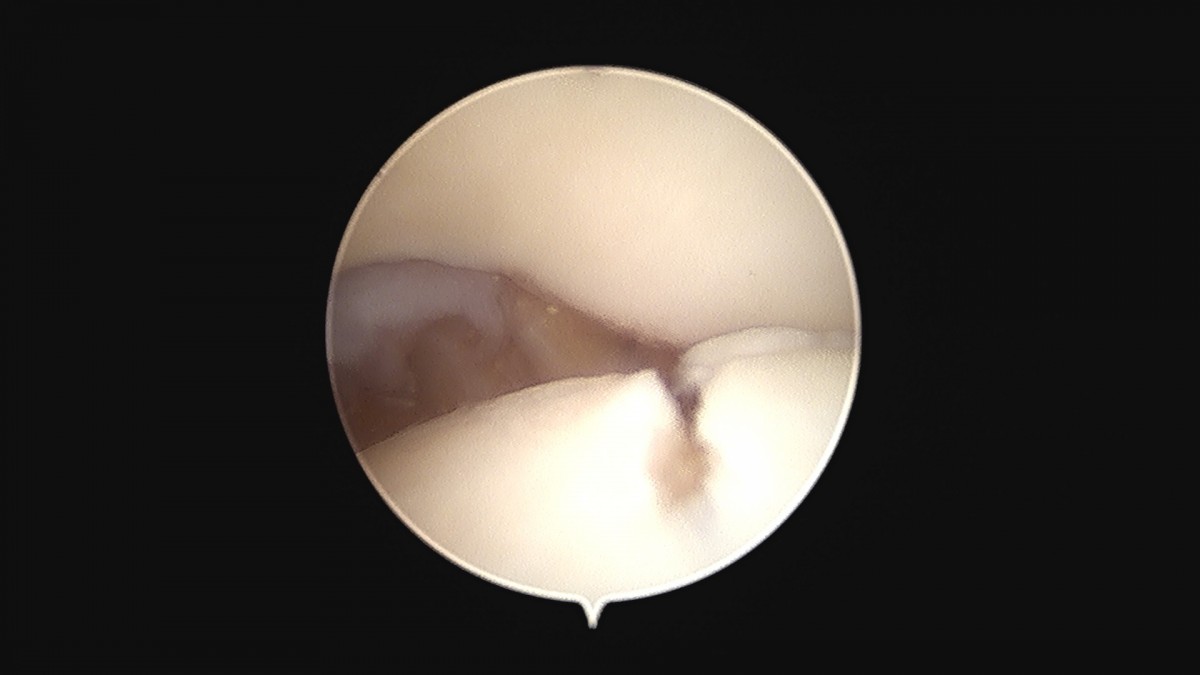

이재상원장님 무릎 변연절제술 권오O 환자

작성자 최고관리자 댓글 0건 조회 373회 작성일 25-09-16 16:11